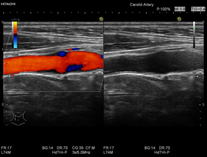

超音波検査

超音波検査とは

体の表面から人の耳には聞こえない音(超音波)を当て、体内の組織にぶつかってはね返ってきた音を画像に映し出す検査です。エコー検査とも呼びます。超音波検査は放射線による被ばくなく施行でき、痛みも伴わず体内をリアルタイムに観察できるという長所があります。

短所は、検査を受ける方の体型や腸管ガスが多い場合に描出能が悪いことがあります。

超音波検査では様々な部位、臓器の観察が可能です。

血管 | 心臓・頸部・手足の末梢血管など |

検査部位にゼリーを塗り、超音波を受発信する探触子(プローブ)を肌に当てて検査をします。検査時間は部位によって異なりますが20~50分程度です。

当院で使用している機器